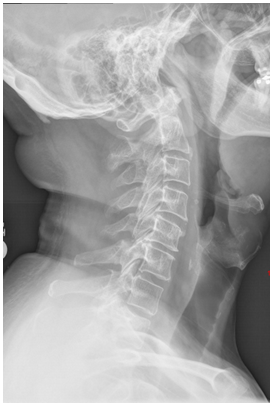

Critique the lateral cervical spine seen in Figure 2–1 and select the most correct statement below. A - The chin has been depressed too much. B - The chin needs to be extended more. C - The head is tilted. D - The shoulders are not depressed enough.

D - The shoulders are not depressed enough. The lateral projection of the cervical spine requires that the MSP be parallel to the IR and the MCP be perpendicular to the IR. The chin must be elevated enough so as not to superimpose the mandibular angles on cervical structures—yet not so much that the base of the skull obscures cervical structures. The degree of flexion/extension is appropriate in this image; no cervical structures are obscured. The vertebrae are symmetrical—no rotation is present. However, C7 is not clearly delineated, and its all-important articulation with T1 is not visible. This indicates that the shoulders are not sufficiently depressed. ``